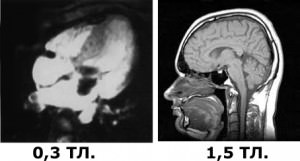

Для прикладу ми з фотографували знімки з двох різних діагностичних центрів. Зліва, апарат з потужністю 0,3 Тл., з іншого боку потужність 1,5 Тл. Навіть людині без вищої медичної освіти зрозуміло що зліва не можливо поставити діагноз, а тим-паче призначити лікування.